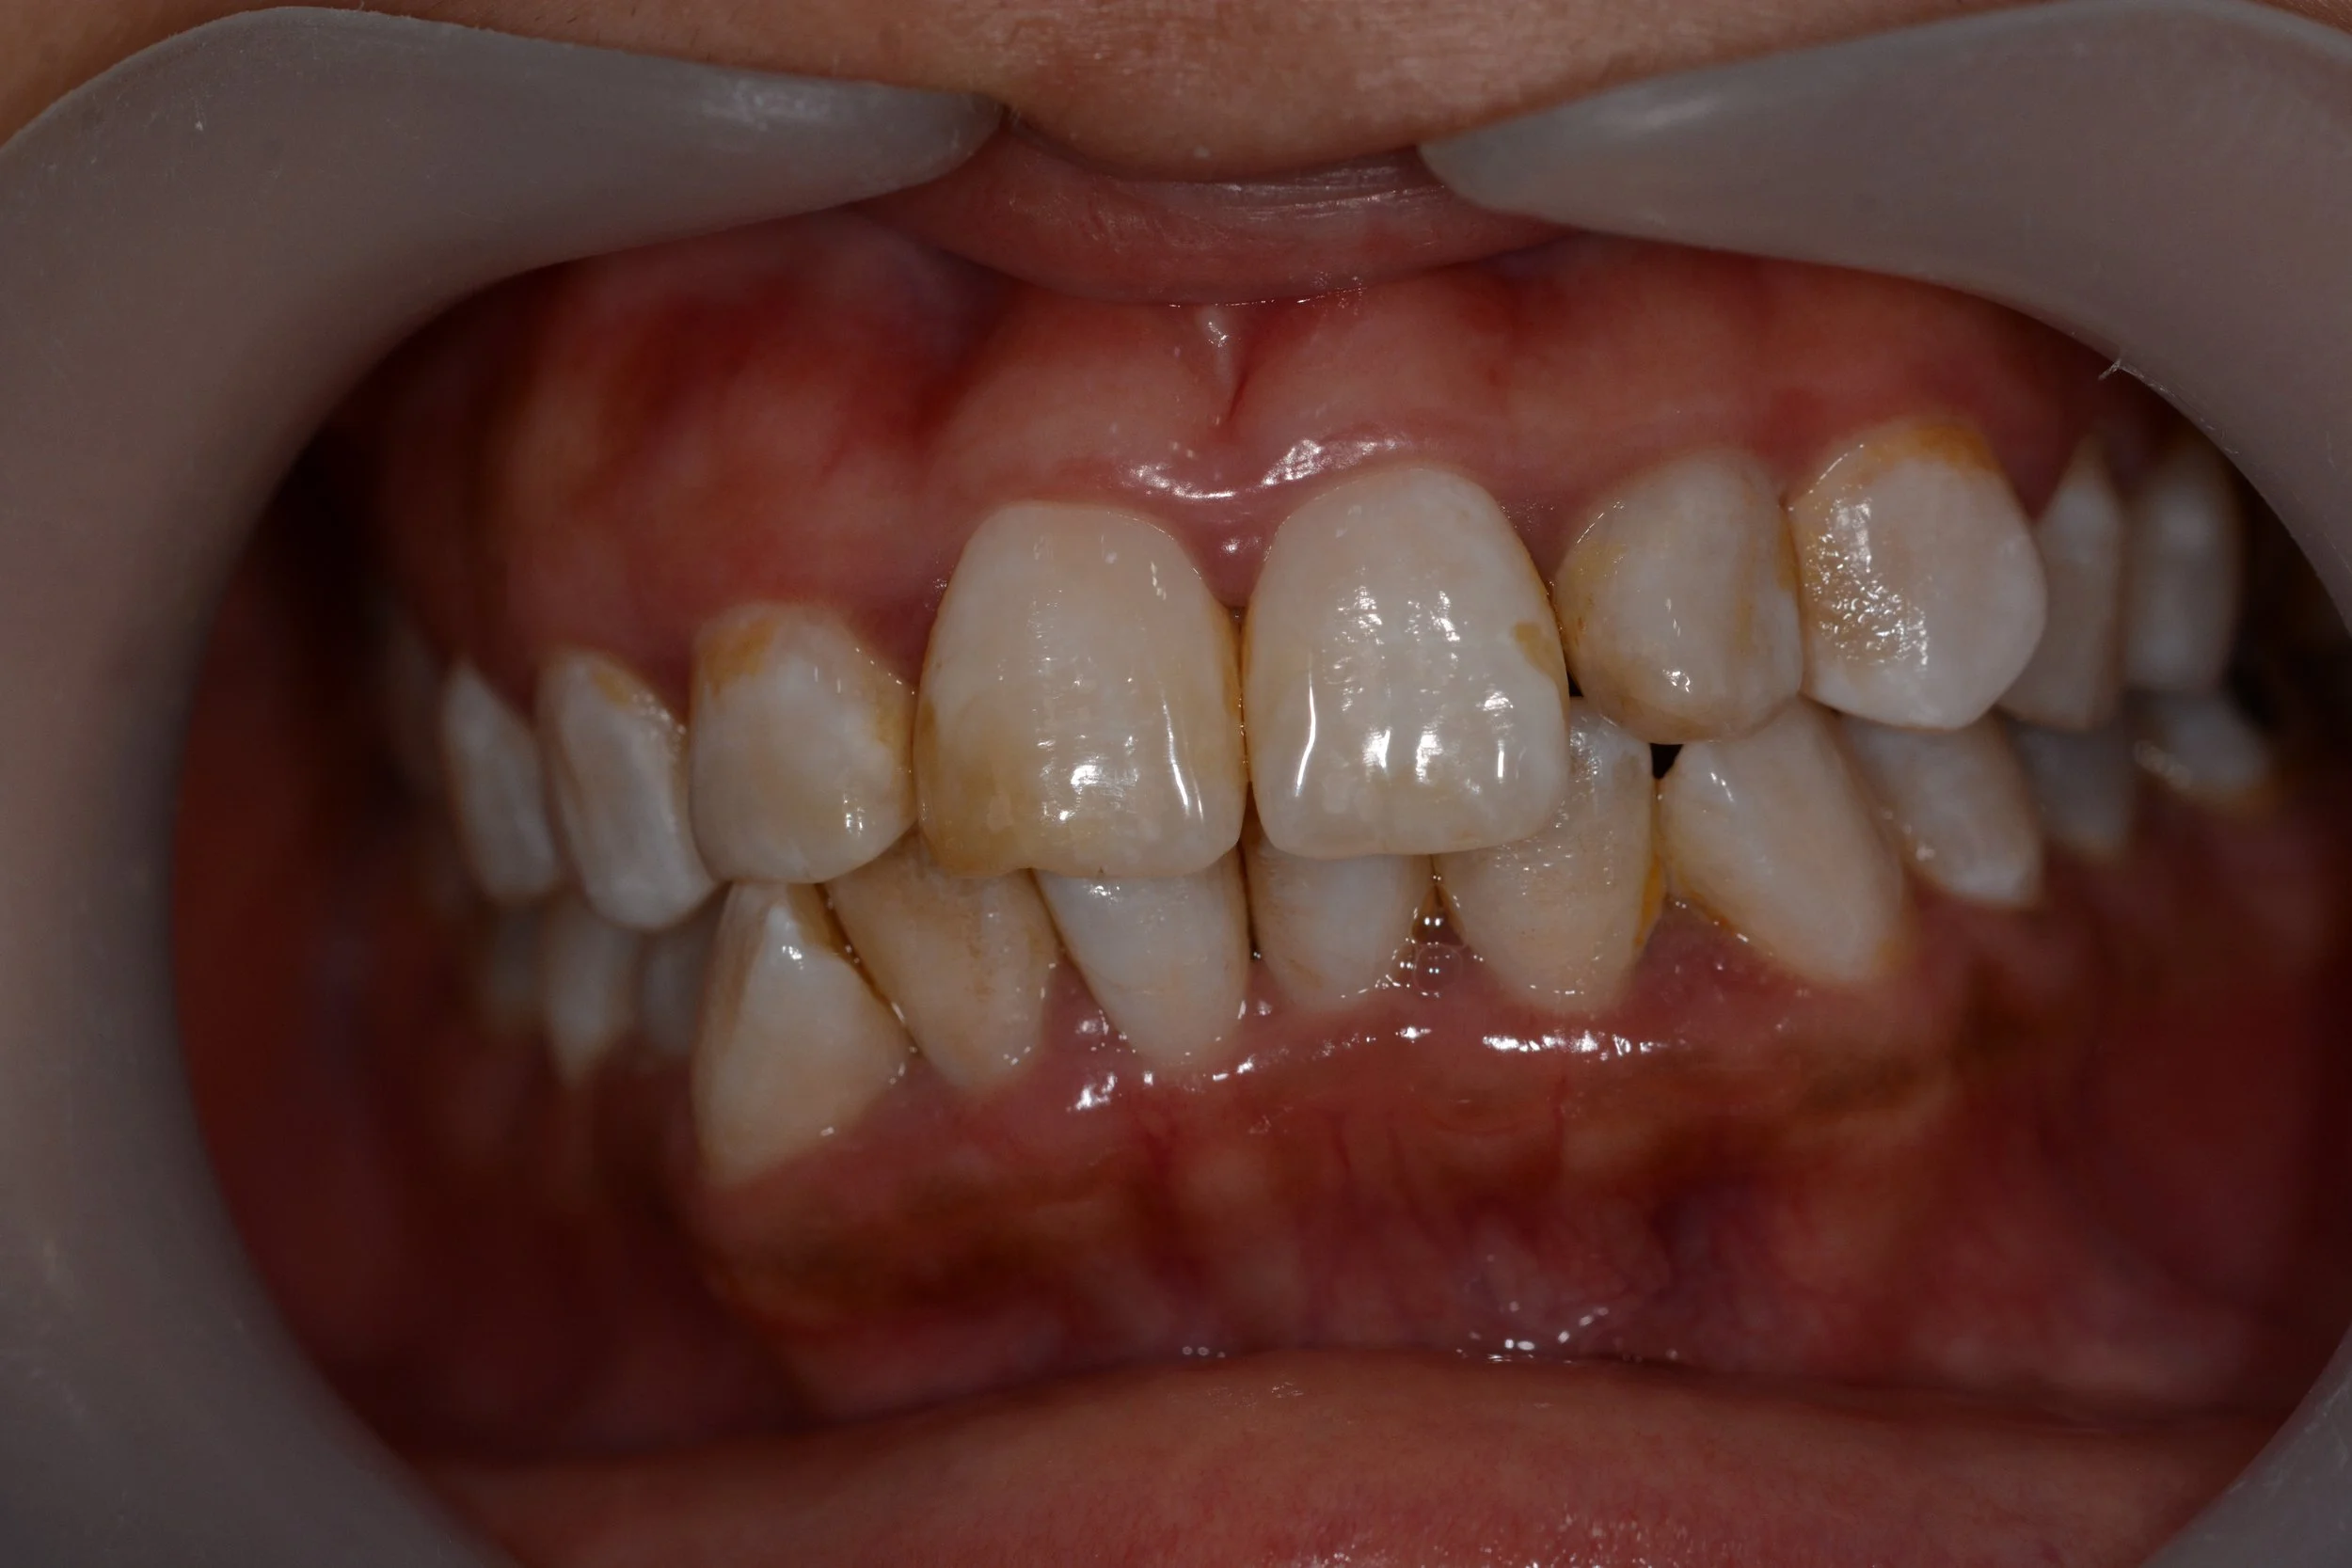

Restoring aesthetics and function of a failing dentition is our main goal. When you smile, it brings us joy.

DSC_0285.JPG

AFTER

MULTIPLE TEETH REPLACEMENT

(WITH DENTAL IMPLANTS)